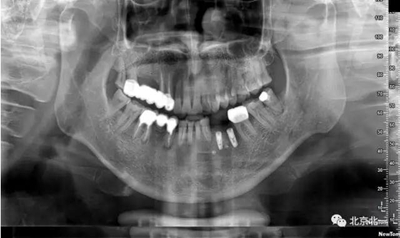

采取骨替代品移植后蓋膜,膜釘固定。

手術(shù)后半年觀察, 成骨良好。

總結(jié):水平骨增量主要解決骨粉固定,骨膜穩(wěn)定以及血供, 穩(wěn)定壓倒一切, 血供成就一切。 僅此而已。 這就是水平骨增量的精髓所在。